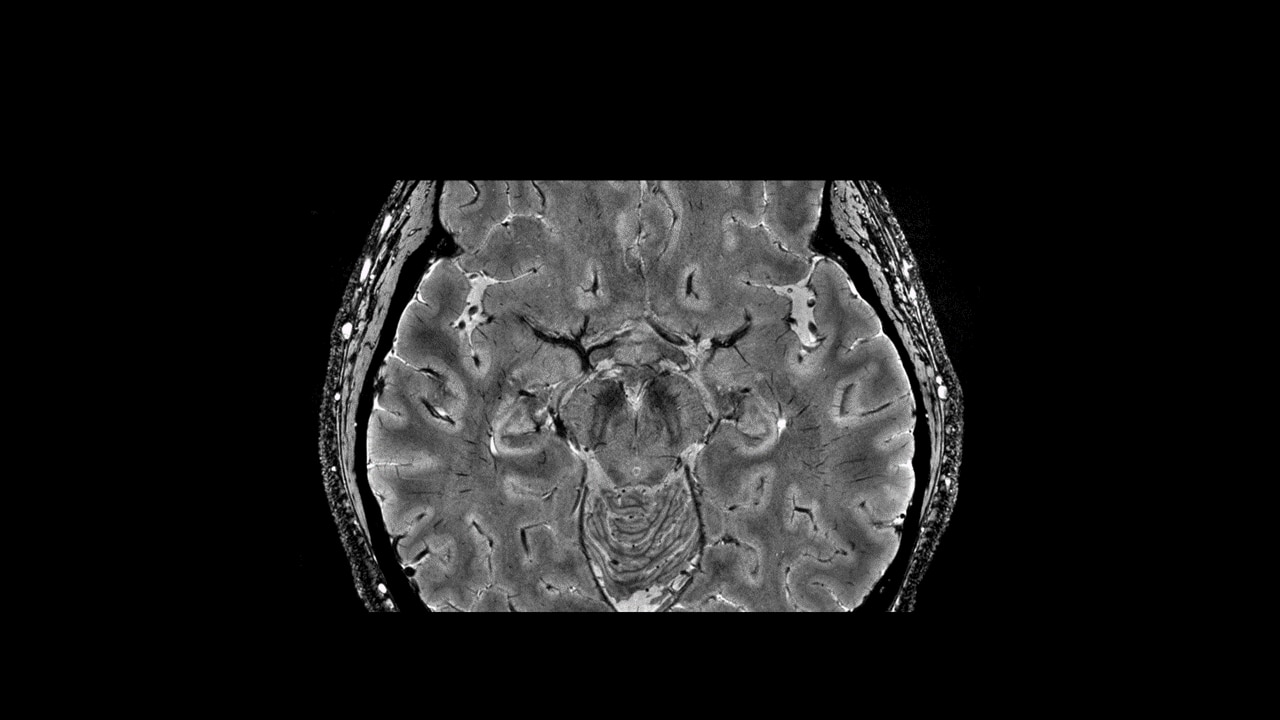

SWAN helps delineate small blood vessels, microbleeds, and large vascular structures in the brain. It applies a multi-TE readout technique that generates more than double SNR and is inherently less affected by the chemical shift compared to conventional SWI techniques. Whole brain acquisition with 3D, sub-millimeter resolution takes ~4 minutes—image reconstruction is virtually instantaneous.